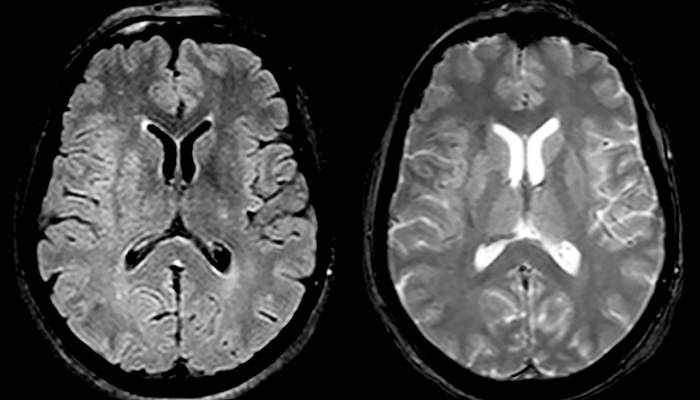

“Ingenia 3.0T provides us very good image quality with high SNR, even if we push the resolution. For example, in FLAIR images we may have an isotropic resolution of 0.9 mm. Ingenia allows us to use 3D T1 TSE with BrainView, which has a better sensitivity than 2D spin echo imaging[2] and 3D gradient echo imaging. Ingenia also provides highly reproducible exams, which is important in MS imaging so that follow-up exams at different time points are done the same way.”

Imaging MS in brain

For MS imaging in the brain, Dr. Savatovsky uses 3D FLAIR as the basic sequence to visualize the lesions and assess the situation and lesion load. “We count the lesions in each location to determine if the criteria of the disease are fulfilled. We use a T2-weighted sequence because our neurologists are used to it. We compare the lesion load on FLAIR with a 3D T1 post-contrast sequence to help us determine whether lesions are old or new. We typically administer the contrast before the patient enters the machine because it shortens the examination time and allows to visualize active lesions that tend to be more visible after several minutes. When a differential diagnosis is difficult, we add sequences such as susceptibility imaging, because some focal MS lesions have a small vein in the center[3].”